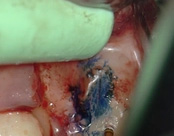

This person saw a specialist and was told the molar tooth needed to be extracted because the root canal failed and was infected. The root canal had been done by an endodontic specialist. The diagnosis was: previous endodontic treatment, chronic periradicular abscess. We did an apicoectomy and saved the patient’s tooth.